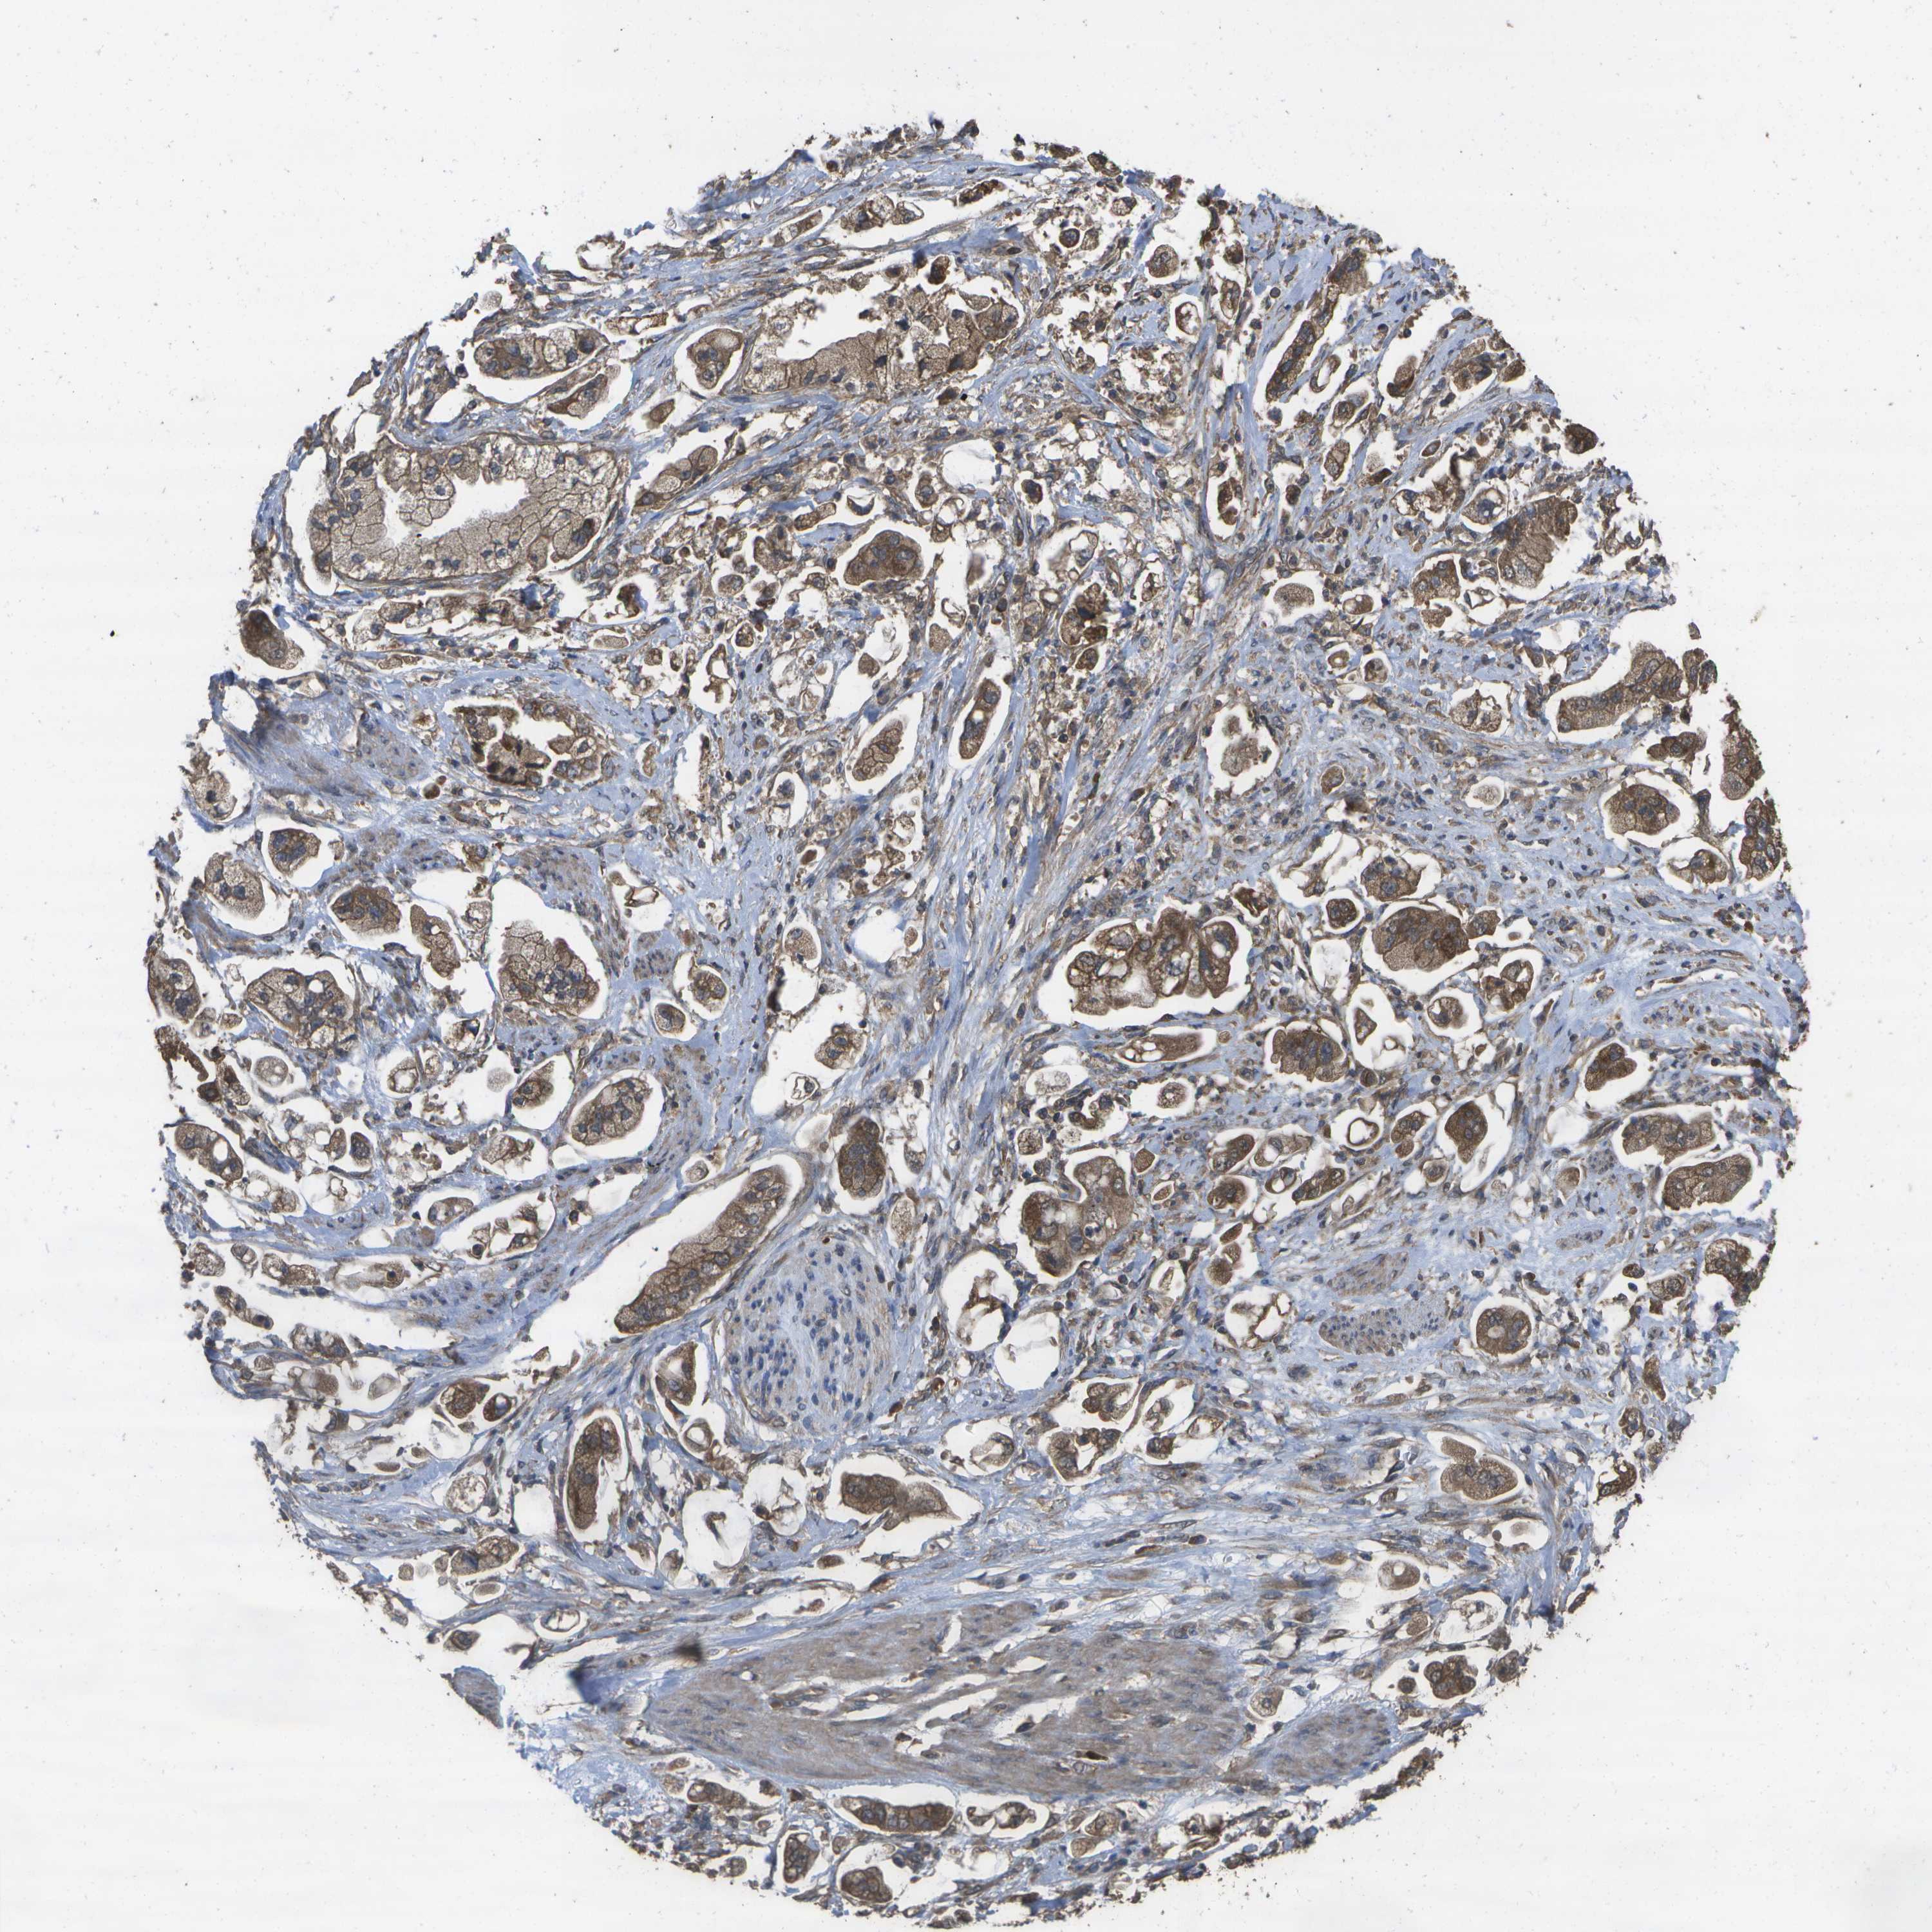

STOMACH CANCER - Protein expressioni

A mouse-over function shows sample information and annotation data. Click on an image to view it in a full screen mode. Samples can be filtered based on level of antibody staining by selecting one or several of the following categories: high, medium, low and not detected. The assay and annotation is described here.

Antibody stainingi

Antibody staining in the annotated cell types in the current human tissue is reported as not detected, low, medium, or high, based on conventional immunohistochemistry profiling in selected tissues. This score is based on the combination of the staining intensity and fraction of stained cells.

Each image is clickable and will lead to virtual microscopy that enables deeper exploration of all samples and also displays staining intensity scores, fraction scores and subcellular localization as well as patient and tissue information for each sample.

Antibody CAB017714

Staining

High

Medium

Low

Not detected

Intensity

Strong

Moderate

Weak

Negative

Quantity

>75%

75%-25%

<25%

None

Location

Nuclear

Cytoplasmic/membranous

Cytoplasmic/membranous,nuclear

Adenocarcinoma, NOS

Adenocarcinoma, High grade